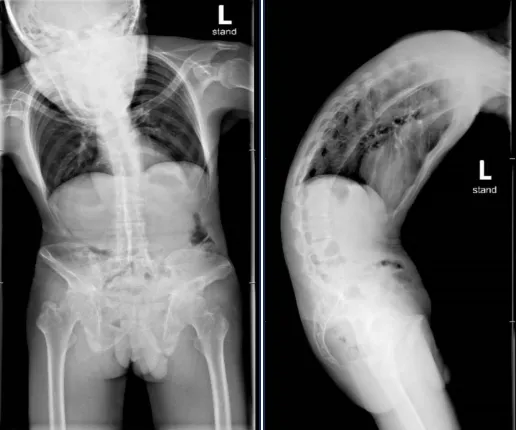

▲患者手术前脊柱正、侧位片

▲患者手术后脊柱正、侧位片